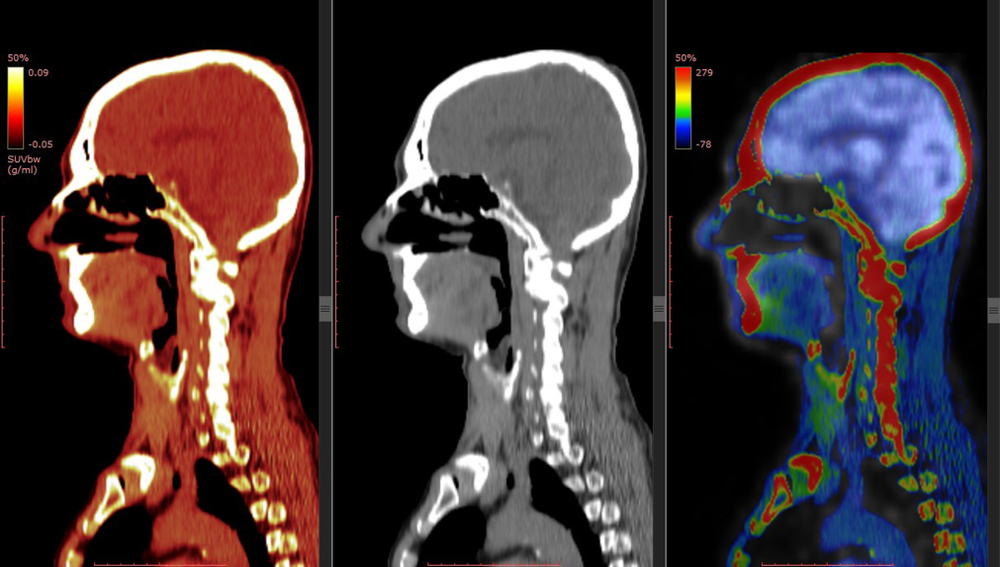

While any insurance denial can be devastating to your treatment plan and your long-term health, a PET scan insurance denial can be particularly damaging. PET (positron emission tomography) scans use radioactive material to create an image that allows a doctor to find cancerous tumors, determine how well a specific cancer is responding to treatment, or diagnose heart disease, brain disorders, and many other serious diseases including Alzheimer’s disease.

A small amount of short-acting radioactive liquid (tracer) is injected into the person receiving the PET scan, then after about 90 minutes of resting quietly, the individual will receive a full-body scan, which typically takes about 20 minutes. Since cancer cells have a higher metabolic rate than typical cells, they will show up as bright spots on the PET scan.

A PET scan denied by insurance may state that there are not enough medical studies showing the PET scan is better than other tests like a much less expensive CT scan. This is simply not true. While a CT scan shows detailed pictures of an individual’s organs and tissues, a PET scan is much more sensitive, and can find abnormal activity and show changes in your body much sooner than any other type of scan, including CT scans and MRIs.